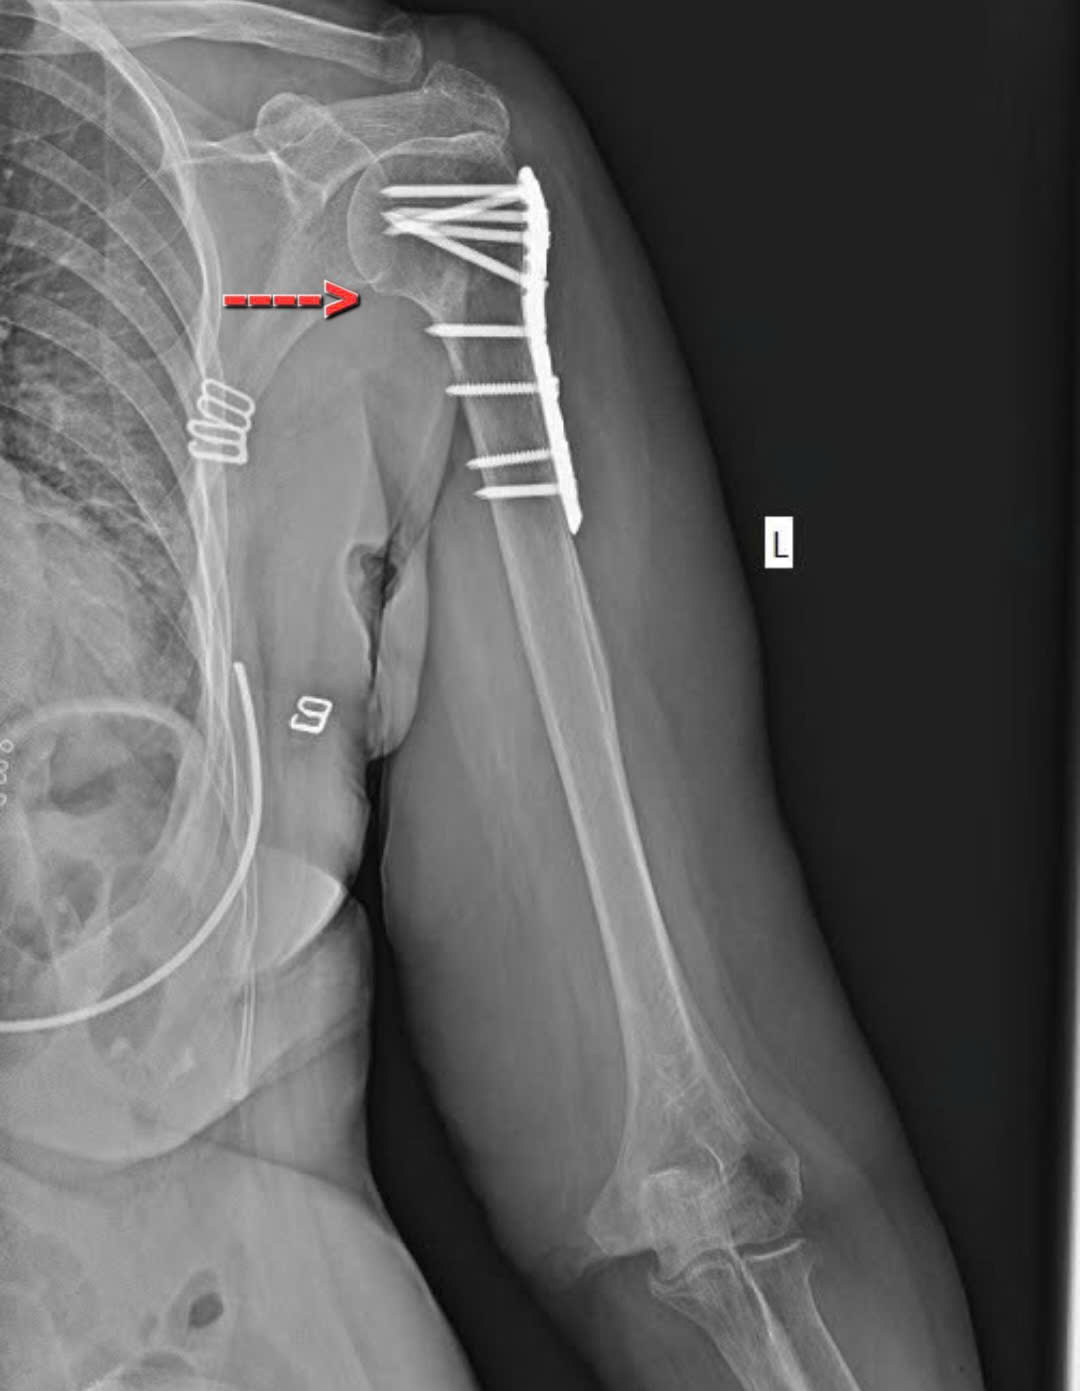

Bệnh nhân nữ 72 tuổi chẩn đoán: gãy kín đầu trên xương cánh tay trái

Kèm theo gãy kín đầu dưới xương quay trái

Được mổ và theo dõi tại Trung tâm y tế Khu vực Thuận An sau 3 tháng xương lành tốt vận động như bình thường. Đây là hình ảnh X quang sau 9 tháng xương lành rất tốt

X quang sau 9 tháng xương gãy lành rất tốt